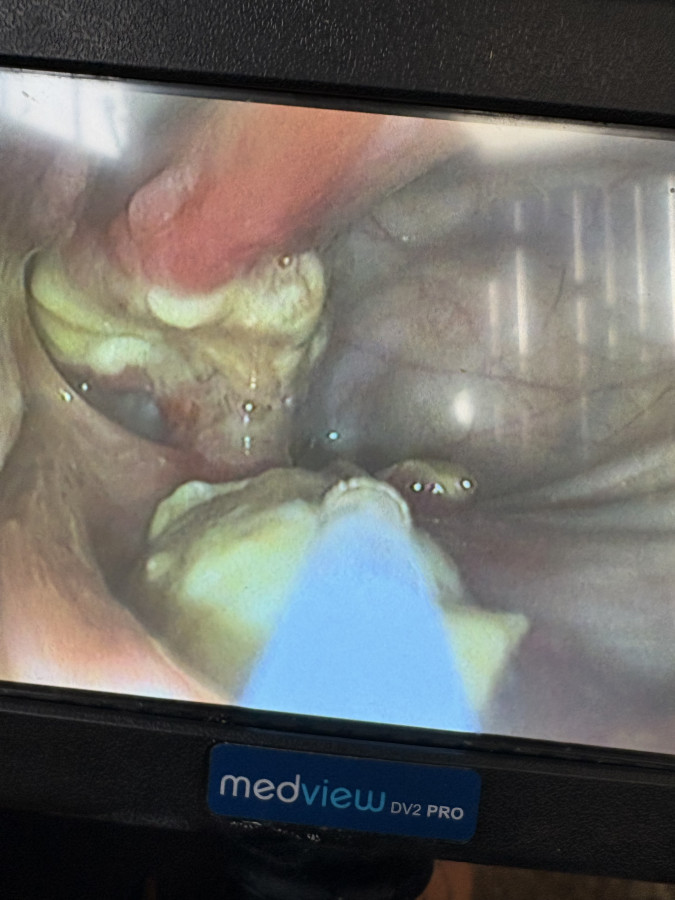

Le champignon est bien présent. Passage samedi dernier - lundi ils ont pu bien voir le champignon qui est bien présent ++

Cliquez pour voir l'image